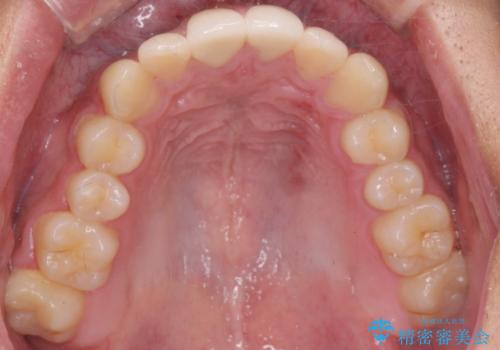

- 20代男性

- 2ヶ月

- 2-5回

- 前歯を良くしたい(綺麗にしたい)との事で来院。

前歯のがたつきを治す治療プランとして

1 矯正を行い歯並びを良くする。(費用と時間がかかる)

2 セラミッククラウンで見た目を良くする(短時間で終わるが歯の向きを無理やり変えるために便宜的に歯の神経を抜く必要がある。健康な歯を削る)

のご提案をしたところ2のプランを選択されたのでセラミック治療を行いました。

- ジルコニアクラウンスペシャル・仮歯 16.5万円×2 精密根管治療(イニシャルトリートメント)・ファイバーコア 8.8万円費用は治療当時の料金となります

見た目が良くなり大変満足して頂けました。